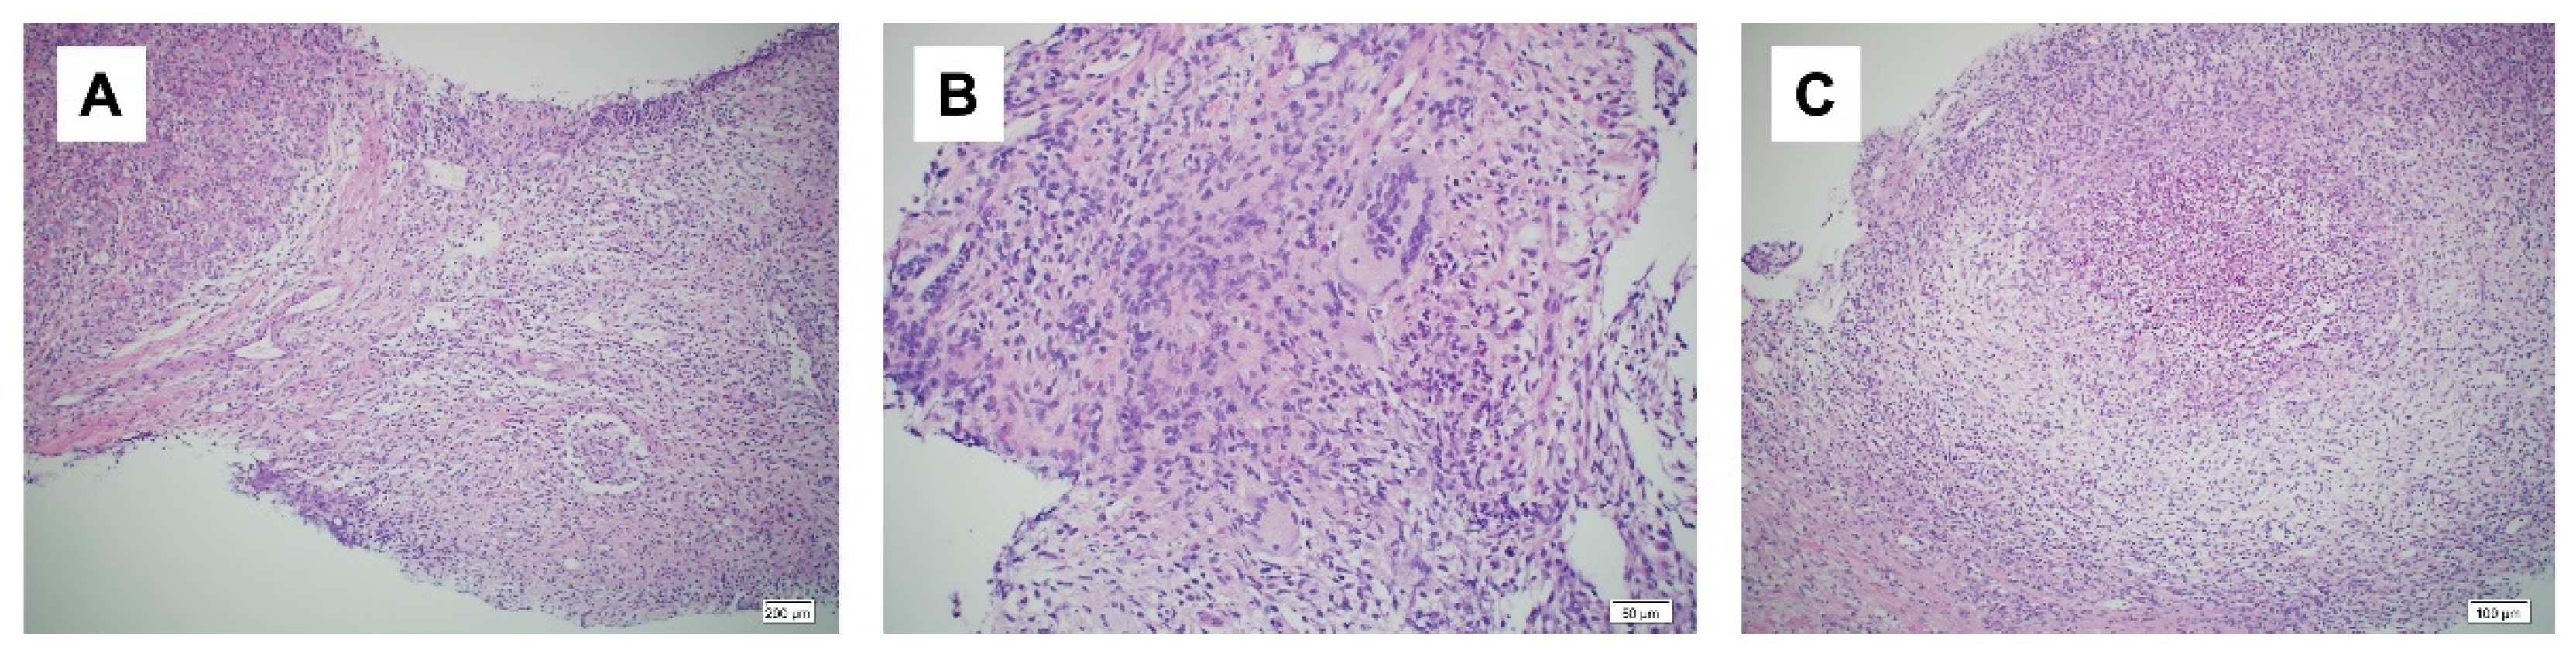

A day after the elective cesarean section, a bacterial culture and needle biopsy of the left mammary gland were performed. The bacterial culture results again revealed the presence of C. kroppenstedtii. A needle biopsy revealed granulomatous mastitis (Figure 3a–c). Based on these examination results, the patient was diagnosed with granulomatous mastitis. One month after surgery, the patient's symptoms flared up again, and she was started on prednisolone 20 mg/day after weaning. Two weeks after starting prednisolone, the dose was reduced to 10 mg/day and the wound healed with iodine ointment. Prednisolone was gradually decreased, the treatment was terminated four weeks after the initial treatment had begun, and the patient was examined during follow up checkups. However, one week later, her symptoms re-emerged and prednisolone was started again at 30 mg/day. The symptoms improved, prednisolone tapered off, and the patient recovered completely after two months. One and a half years after the surgery, no recurrence was observed.

Figure 3. Histopathological findings. a: Non-dysbutyroid epithelial granuloma (hematoxylin-eosin [HE] staining ×10); b: area consisting of a cluster of multinucleated giant cells (hematoxylin-eosin [HE] staining ×20); c: area of an abscess (hematoxylin-eosin [HE] staining ×10).